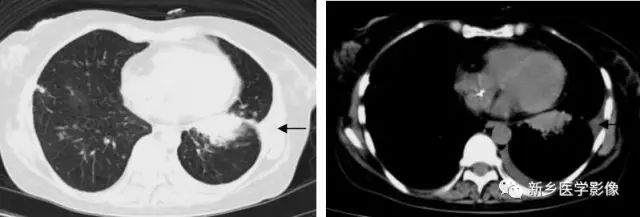

渗出性病变X线及CT图像

胸部X线正位片(a)示左肺纹理增多、模糊;CT肺窗(b)和纵膈窗(c)示两下肺片状高密度影,边缘模糊。

右肺下叶实变CT图:显示空气支气管征(↑)